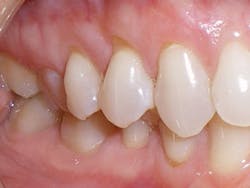

Compare the inclination of the long axis of teeth on #12 before and after treatment.

Figure 3

We find these areas of clefting, recession, and abfraction most often on the buccals of the canines and premolars, as well as occasionally on the buccals of the first molars as a result of lingual inclination. Dentists have made a routine practice of restoring the abfracted missing tooth structure with composite resin restorations. Dentists have also made it a practice to refer these patients to the periodontist for possible grafting procedures to replace the receded gingival tissues. These composite resin restorations and periodontal grafting procedures are classic examples of treating the symptoms instead of treating the cause.

The cause of the recession and abfractions is the patient's malocclusion. Specifically, it is the resulting horizontal force placed on the teeth from the malocclusion. Malocclusions deliver horizontal forces to the posterior teeth, and the result is early recession and abfractions that will continue to deteriorate until the cause is treated.